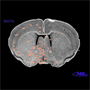

periventricular nucleus of the hypothalamus

Nissl stain of

coronal section in

mouse